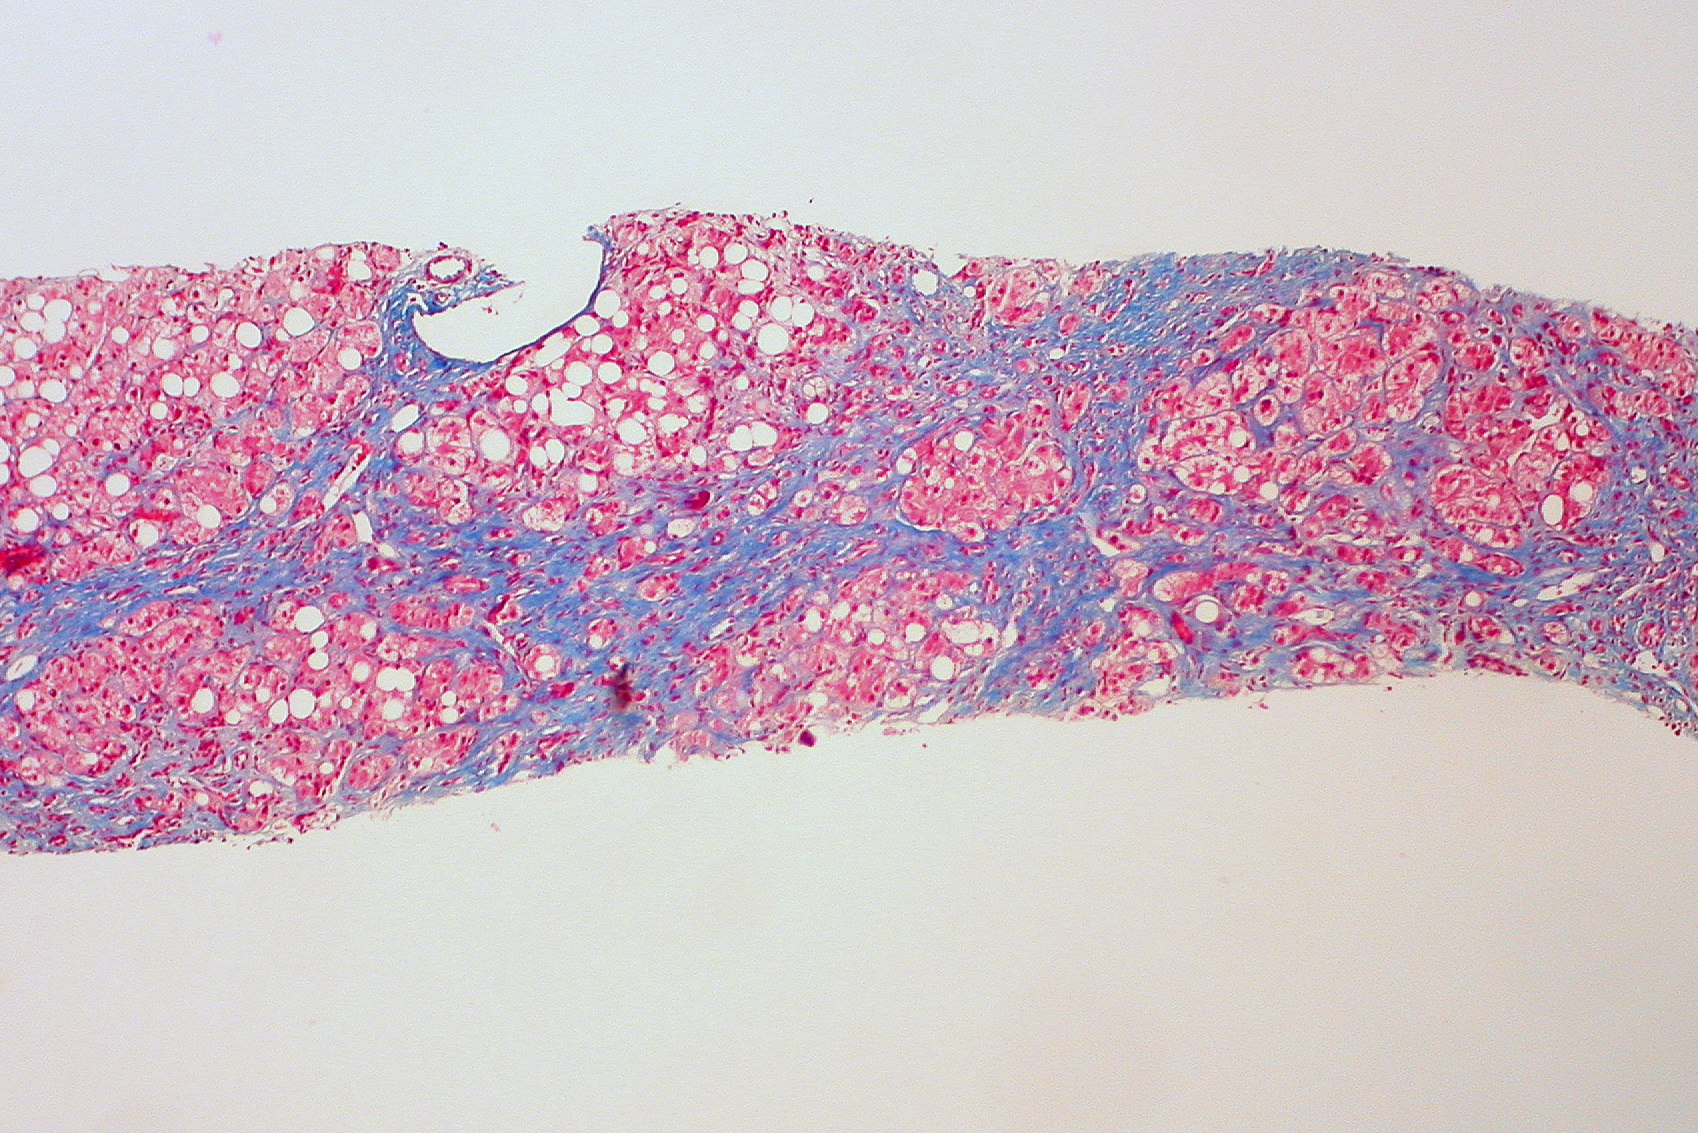

3. 2. 병리학

간경변증의 병리학적 특징은 정상 조직을 대체하는 흉터 조직의 발생이며, 이 조직은 일반적으로 소엽으로 구성된다. 이 흉터 조직은 장기를 통한 혈액의 문맥 흐름을 막아 혈압을 상승시킨다.[58] 이는 문맥 고혈압으로 나타나며, 문맥 순환과 전신 순환 사이의 압력 기울기가 높아진다. 이러한 문맥 고혈압은 간세포에서 간의 인접한 동맥혈관으로의 혈류 감소와 림프 생성 증가로 이어져 림프가 세포외 공간으로 누출되어 복수를 유발한다.[58] 또한 심장 귀환과 중심 혈액량을 감소시켜 레닌-안지오텐신 시스템(RAAS)을 활성화하여 신장이 나트륨과 물을 재흡수하게 하여 체액 저류와 복수를 더욱 악화시킨다. RAAS의 활성화는 또한 신장 혈관 수축을 유발하고 신장 손상을 일으킬 수 있다.[58]정상적으로 비타민 A를 저장하는 성상 세포는 간경변증 발생에 중요한 역할을 한다. 염증으로 인한 간 조직 손상은 성상 세포를 활성화시켜 근섬유아세포를 생성하여 섬유증을 증가시키고 간 혈류를 방해한다.[59] 또한, 성상 세포는 TGF 베타 1을 분비하여 섬유성 반응과 결합 조직의 증식을 유발한다. TGF-β1은 간 성상 세포(HSC)를 활성화시키는 과정에 관여하며 섬유증의 정도는 TGF β 수치 증가에 비례한다. ACTA2는 HSC의 수축성을 향상시켜 섬유증을 유발하는 TGF β 경로와 관련이 있다.[60] HSC는 기질 금속 단백분해효소(MMPs)의 자연 발생 억제제인 TIMP1 및 TIMP2를 분비하여 MMP가 세포외 기질의 섬유성 물질을 분해하는 것을 방지한다.[61][62]

이러한 과정이 계속되면 섬유성 조직 띠(격막)가 간세포 결절을 분리하여 결국 전체 간 구조를 대체하여 혈류가 감소한다. 비장이 울혈되고 비장비대가 발생하여 정상적인 혈액 응고에 필요한 혈소판을 보유하게 된다. 문맥 고혈압은 간경변증의 가장 심각한 합병증의 원인이다.

간 생검에서는 재생 결절을 동반한 섬유화된 간 조직을 관찰한다. 재생 결절의 크기가 3mm보다 작은 것은 소결절성 간경변으로 분류되며, 알코올성 간경변에서 많이 보인다. 3mm 이상의 것은 대결절성 간경변으로 분류되며, 바이러스성 간경변에서 많이 보인다. 다만, 초음파 검사나 복부 CT 검사 등 비침습적인 영상 진단 기술의 발전에 따라, 침습적인 간 생검은 간경변 진단에 있어서 그 중요성이 옅어지고 있다. 간 생검이 필요한 경우는, 간경변에 동반하여 간암으로 보이는 종양 조직으로 의심되는 것이 영상 진단에서 발견되었을 때이다.